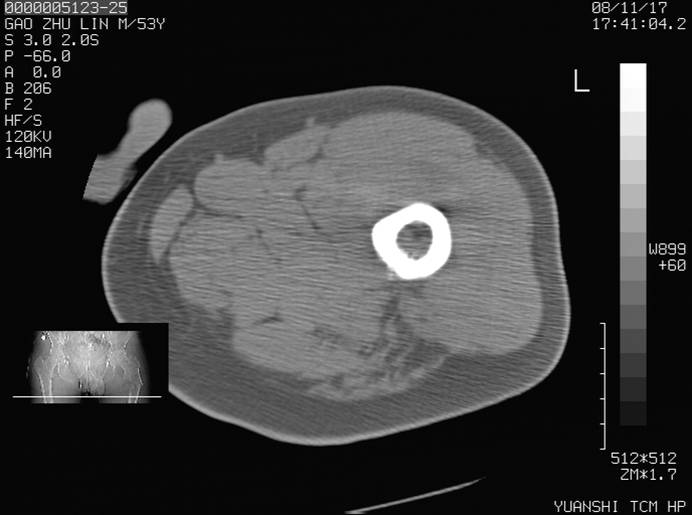

标题: CT16696:M53Y,左股骨上段骨折。 [打印本页]

标题: CT16696:M53Y,左股骨上段骨折。

左股骨上段外伤1个小时,左股骨上段疼痛。村医以腰椎间盘病变给以按摩及理疗数天。

图像不太清楚,左股骨上段外伤性骨折?病理性骨折?

左股骨上段粉碎性骨折

左股骨上段粉碎性骨折;建议上传骨窗看看是不是病理性的啊!

左股骨上段粉碎性骨折,不排除病理性骨折可能。

考虑骨肉瘤伴病理骨折

考虑:骨肉瘤伴病理骨折.

病理性骨折,考虑转移所致.